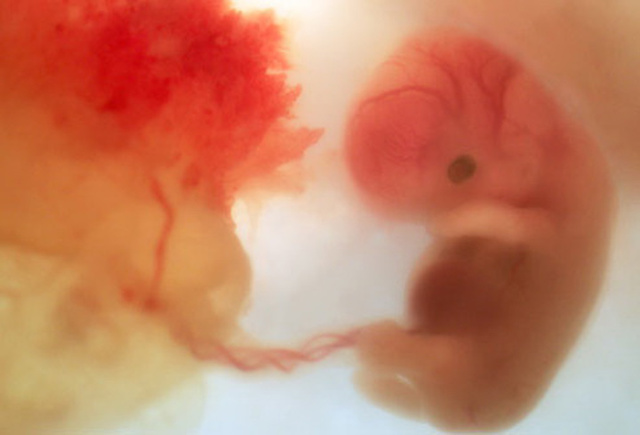

• Estado embrionario

Estado embrionario

La mórula ha acabado su viaje a través de la trompa de Falopio y alcanza el interior del útero. Comienza una nueva transformación celular en la que las células se dividen en dos grupos. Uno de ellos comienza a formar el blastoembrión, que es lo que será el futuro embrión. El otro grupo de células van a componer lo que se denomina trofoblasto, que es la capa que va a proteger el embrión y a su vez le va a ayudar a implantarse en el endometrio.

El embrión se muestra en forma de C. La cabeza destaca a simple vista. Ojos y orejas comienzan a formarse. El corazón comienza a desarrollar sus válvulas y tabiques. Empieza la formación de órganos digestivos.

Se cumple casi el mes desde la concepción. El embrión alcanza un tamaño de 6 milímetros. Comienzan a organizarse funciones vitales, tales como la respiración. Se forman la boca y la lengua. Aparecen unos pequeños estigmas que darán origen a las extremidades. Se forman las primeras células de la piel.

Durante esta etapa, la cabeza y el cerebro se desarrollan rápidamente. Comienza la división cerebral de los dos hemisferios. El embrión alcanza un tamaño de 12 milímetros.